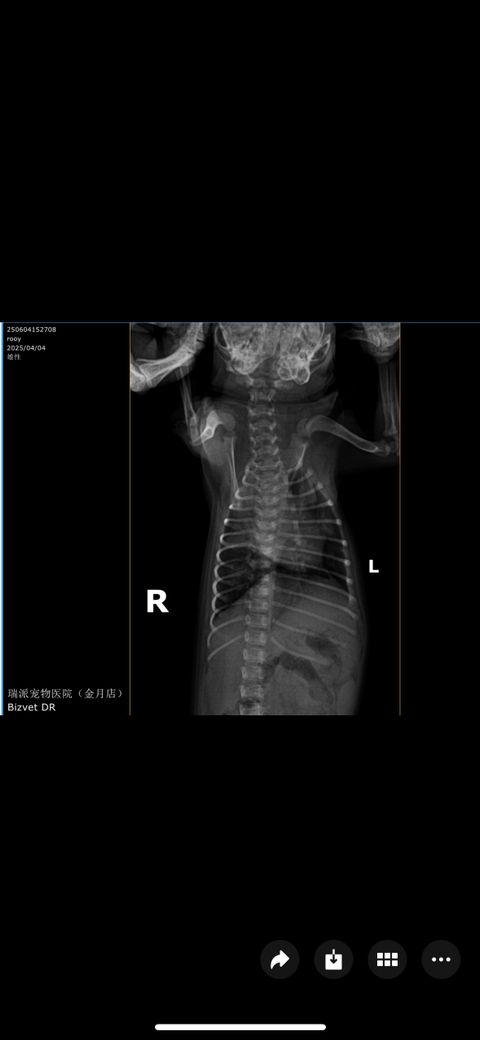

순서대로 2일 간격 엑스레이 사진입니다 ㅠ

점점 안좋아 지는게 맞나요?!

기침은 계속해요.. 의사말로는 마지막 오늘 엑스레이 보고 폐의변화가 있어 숨쉬기 힘들어 할꺼다 하는데 ㅠ 여기가 중국이라서 제대로 치료가 되는지 걱정입니다

폐 전엽부가 다 먹혀버린 매우심한 세균성 폐렴 혹은 인플루엔자 감염이 의심됩니다.

집중적인 처치가 필요한 상태이니 주치의와 잘협의하게 집중 처치하시기 바랍니다.